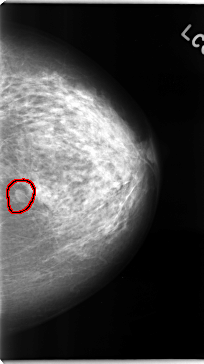

FILE: C_0102_1.LEFT_MLO.OVERLAY

TOTAL_ABNORMALITIES 1

ABNORMALITY 1

LESION_TYPE MASS SHAPE OVAL MARGINS CIRCUMSCRIBED

ASSESSMENT 3

SUBTLETY 5

PATHOLOGY BENIGN

TOTAL_OUTLINES 1

BOUNDARY